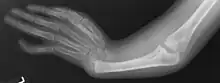

Radial ray malformations

This is characterized by hand and arm abnormalities. The following are specific characteristics:

- Malformed or absent (aplasia) thumb

- A thumb that looks more like a finger

- Partial or complete absence of a radius

- Shortening and radial deviation of the forearms

- Triphalangeal thumb

- Duplication of the thumb (preaxial polydactyly)